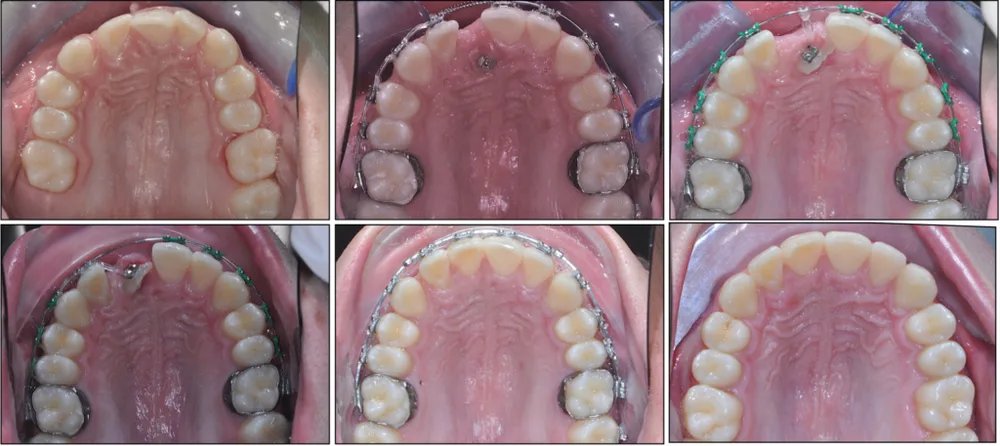

Spesso sono necessari apparecchi ortodontici per poter aiutare questi denti a ritrovare la loro strada. In alcuni casi è necessaria anche una piccola collaborazione chirurgica per esporre il dente e applicarvi un attacco ortodontico.

Una volta esposto chirurgicamente il dente incluso, si applica un attacco ortodontico che permette di guidarlo gradualmente verso la sua posizione corretta nell'arcata.

Il trattamento richiede un lavoro di squadra tra l'ortodontista e il chirurgo orale, con tempistiche pianificate con cura per ottimizzare il risultato.